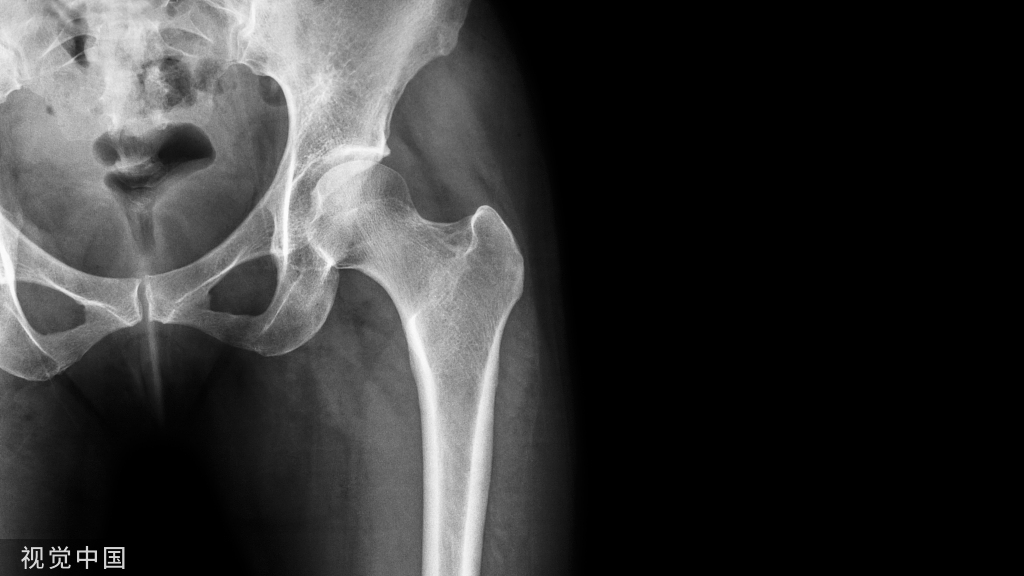

克氏针作为工具使用早期主要用于骨牵引术,如:跟骨牵引、胫骨结节牵引、股骨髁上牵引、尺骨鹰嘴牵引等。